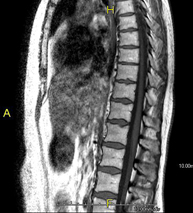

Prova diagnòstica no invasiva que consisteix en l'obtenció d'imatges d'alta definició anatòmica de la columna dorsal mitjançant l'ús d'un camp electromagnètic i ones de ràdio (com un emissor i un receptor). No utilitza radiació ionitzant. Indicacions: traumatisme, problemes degeneratius, hèrnies, tumors. - RM de Columna lumbar

Prova diagnòstica no invasiva que consisteix en l'obtenció d'imatges d'alta definició anatòmica de la columna lumbar i sacre mitjançant l'ús d'un camp electromagnètic i ones de ràdio (amb un emissor i un receptor). No utilitza radiació ionitzant. Indicacions: traumatismes, ciàtica, hèrnies discals, tumors, infeccions - RM Mielografia

Prova diagnòstica no invasiva que consisteix en l'obtenció d'imatges d'alta definició anatòmica de la columna cervical, mitjançant l'ús d'un camp electromagnètic i ones de ràdio (amb un emissor i un receptor). No utilitza radiació ionitzant. Indicacions: traumatisme, degeneració de la columna i hèrnies. - RM Columna Dorsal

Prova diagnòstica no invasiva que consisteix en l'obtenció d'imatges d'alta definició anatòmica de la columna dorsal, mitjançant l'ús d'un camp electromagnètic i ones de ràdio (amb un emissor i un receptor). No utilitza radiació ionitzant. Indicacions: traumatisme, problemes degeneratius, hèrnies i tumors. - RM Columna Lumbar

Prova diagnòstica no invasiva que consisteix en l'obtenció d'imatges d'alta definició anatòmica de la columna lumbar i sacre mitjançant l'ús d'un camp electromagnètic i ones de ràdio (amb un emissor i un receptor). No utilitza radiació ionitzant. Indicacions: traumatismes, ciàtica, hèrnies discals, tumors i infeccions. - RM de Sacre-còccix